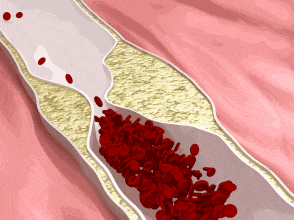

冠状动脉钙化常发生在有冠状动脉粥样硬化斑块形成的部位,是冠状动脉粥样硬化的重要标志,严重冠脉钙化预示着患者发生心梗的风险较高。

如果能将血压、血脂、血糖等控制在理想范围内,养成良好的生活习惯,减少发病的危险因素,能最大程度地预防冠脉钙化,延缓病变进展。